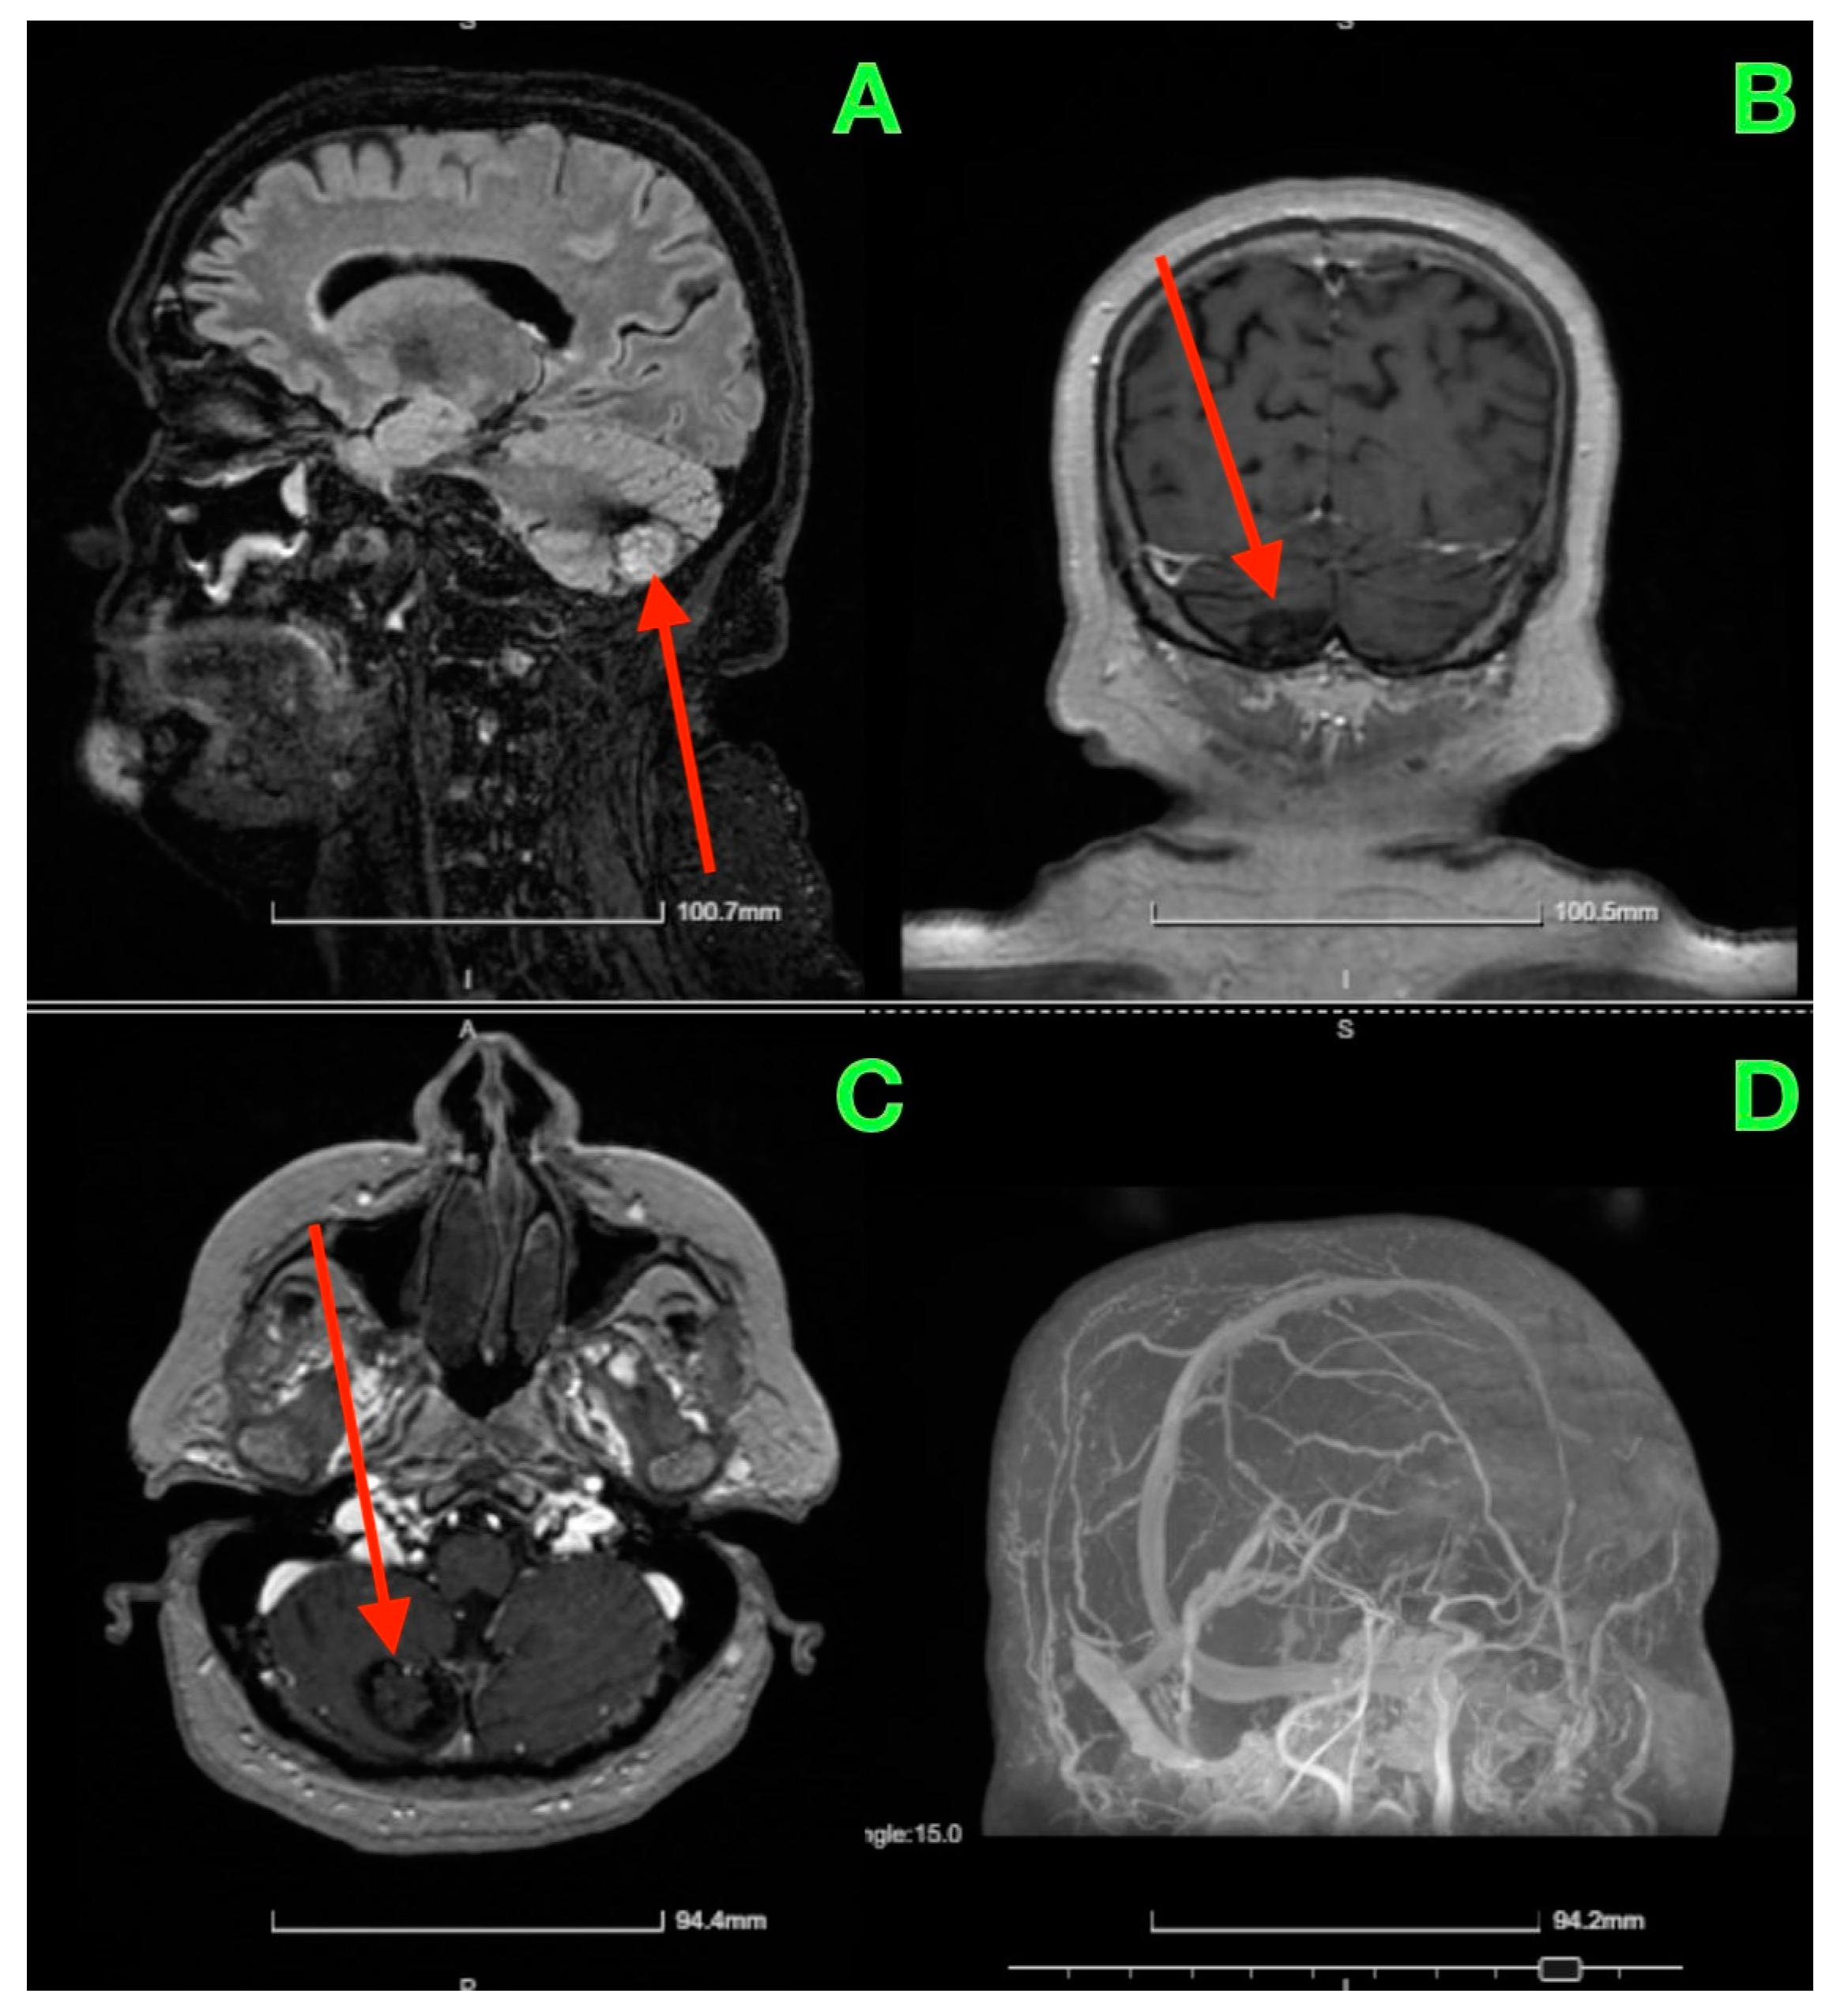

Given the patient’s symptoms and neurological findings, an MRI scan of the brain was performed to further evaluate potential cerebellar or vestibular pathology. The MRI revealed a well-circumscribed cavernous malformation (cavernoma) located in the right cerebellar hemisphere (Figure 1 and Figure 2). The lesion appeared hyperintense on T2-weighted imaging, with a peripheral rim of hemosiderin, suggestive of prior microhemorrhages. The lesion measured approximately 1.5 cm in diameter and was localized to the posterior fossa, without any evidence of acute hemorrhage or mass effect. The surrounding cerebellar structures, including the brainstem, showed no significant compression or deviation. Magnetic resonance angiography (MRA), performed to rule out vascular anomalies, confirmed the absence of arteriovenous malformations or other vascular abnormalities (Figure 1D and Figure 2D). The lesion was determined to be isolated, with no direct involvement of the major cerebellar arteries or veins.

Figure 2. The red arrow highlights the cerebellar cavernous malformation (CCM) located in the right cerebellar hemisphere. This lesion is characterized by its hypointense signal on T1-weighted MRI images (AC), consistent with prior microhemorrhages and hemosiderin deposition surrounding the malformation. The lesion’s distinct margins and location, without significant mass effect on adjacent structures such as the brainstem and fourth ventricle, are emphasized by the arrow. The MRA (D) further confirms the absence of vascular anomalies, distinguishing the lesion as a solitary cavernoma without associated arteriovenous malformation.